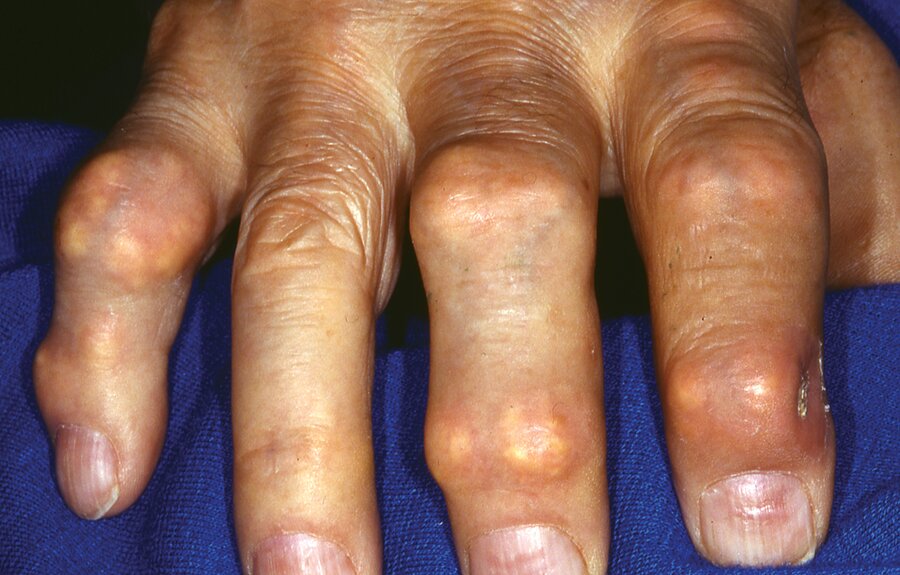

Tophaceous gout (will accept tophi or gout)